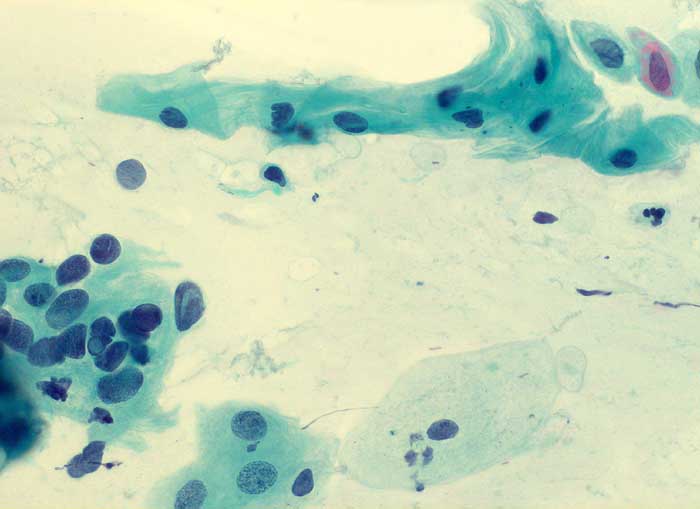

PathoPic – image database / PathoPic ID 6113 - ASCUS

ASCUS

Zervixabstrich: hoher Epithelaufbau. Nicht sicher klassifizierbare Plattenepithelien mit vergrösserten hyperchromatischen Kernen und mittelbreitem Zytoplasmasaum.

Keine histologische Untersuchung. Weitere zytologische Kontrollen unverdächtig.